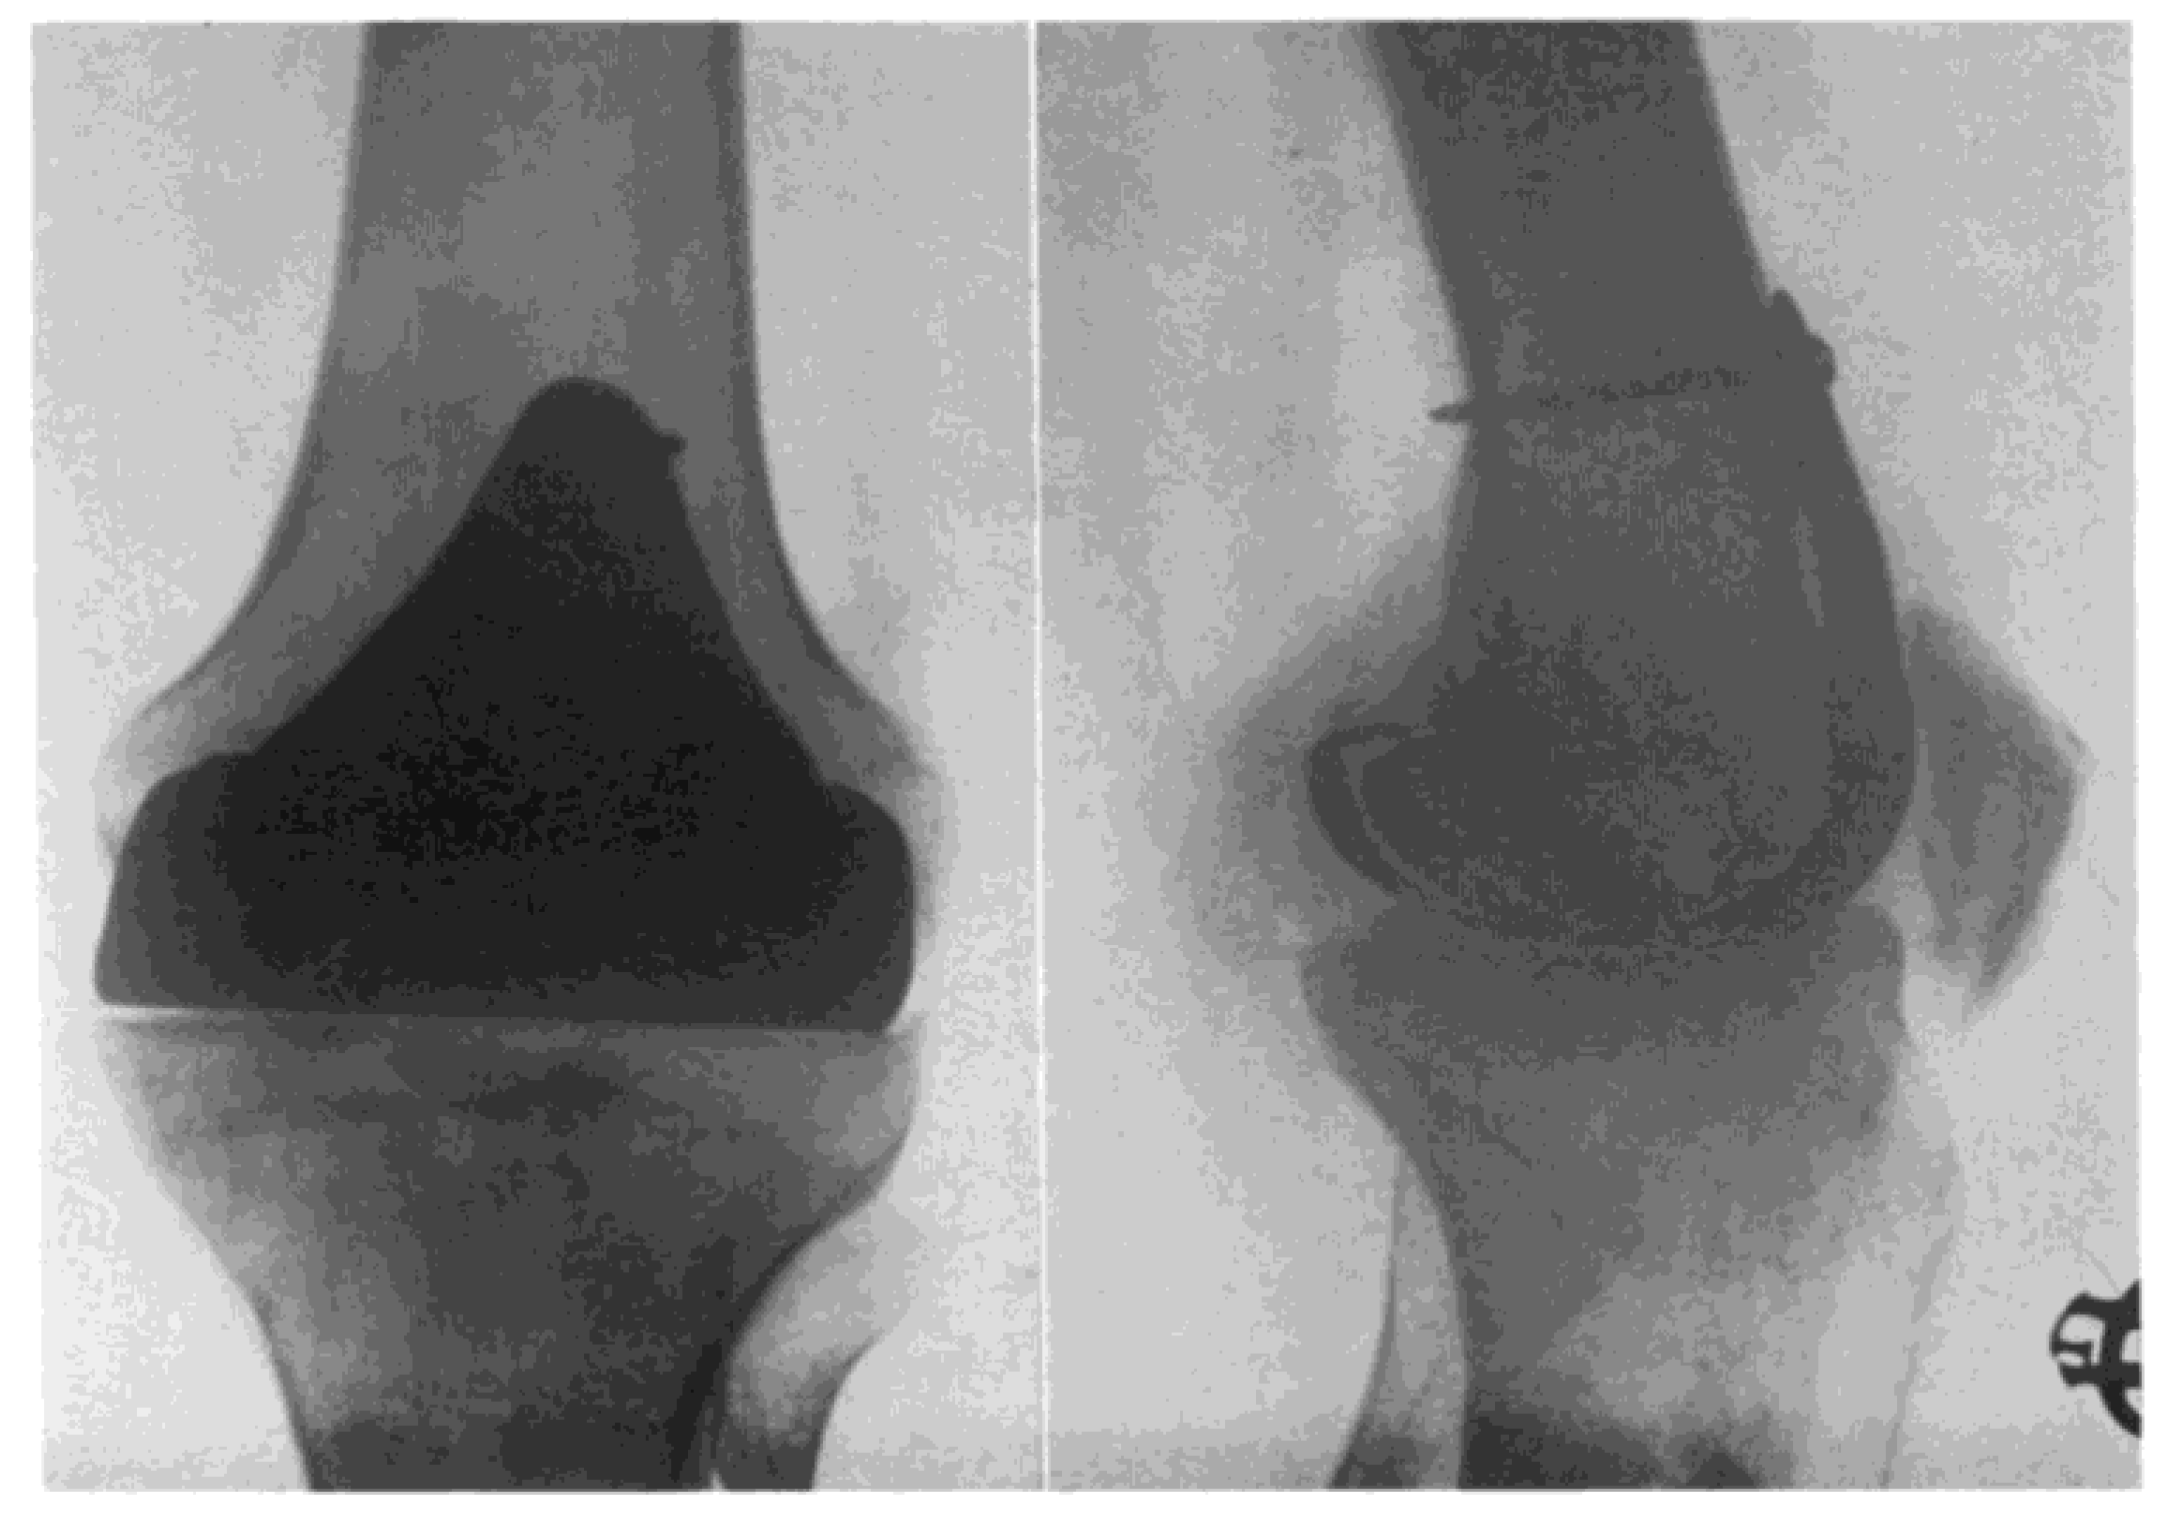

Duncan Clark McKeever, another American orthopaedic surgeon from Valley Falls, Kansas, could be credited as the one who developed the very first metallic tibial plateau unicompartmental replacement in 1952 when he introduced his Vitallium tibial plateau replacement (16) (Figure 4). Although Duncan McKeever’s early results were promising, he could not continue his work as he tragically died in a car accident soon after operating on his 40th patient (16).

Figure 4. Duncan McKeever tibial plateau replacement - 1952. Reprinted from McKeever D. 1960 (16) Copyright 2022 with permission from Wolters Kluwer Health, Inc.